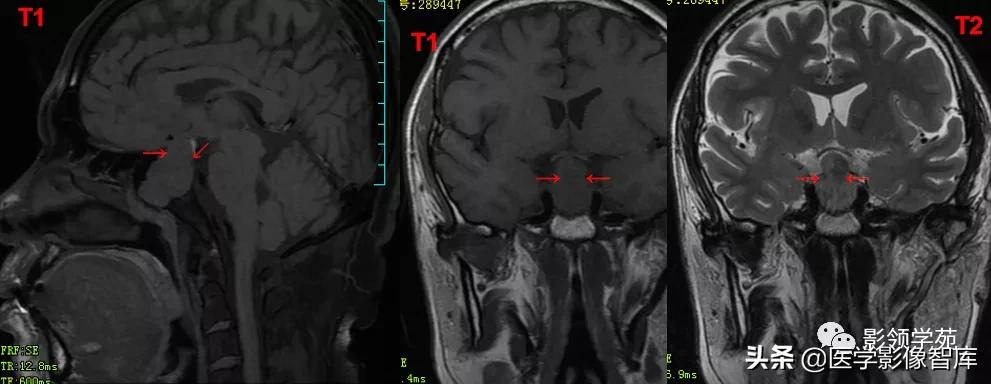

男 49岁, 肢端麻木2月。偶头晕头痛

鞍内及鞍上见一类圆形实性占位病变,边界尚清楚,密度欠均匀,CT值约41-58HU。垂体窝扩大,鞍背骨质稍变薄。

鞍区见一较大肿块,形态不规则,边界清楚,T1WI呈等信号,T2WI呈高低混杂信号;

矢状面和冠状面上可见典型束腰征、雪人征(腺瘤通过鞍膈向上生长时,由于受到鞍膈的限制而形成对称的切迹)。

病灶不均匀 明显强化。视交叉、垂体柄受压上移。